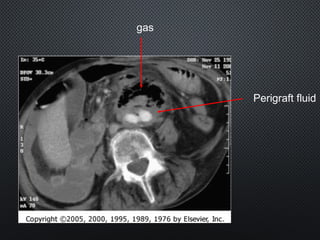

gas

Perigraft fluid

duodenum graft